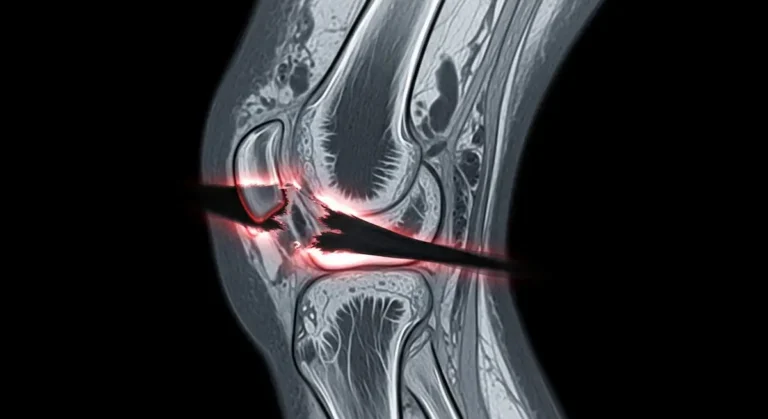

Lesões do LCP: tudo o que você precisa saber

As lesões do LCP afetam a estabilidade do joelho e podem surgir em traumas esportivos ou acidentes. Com base em…